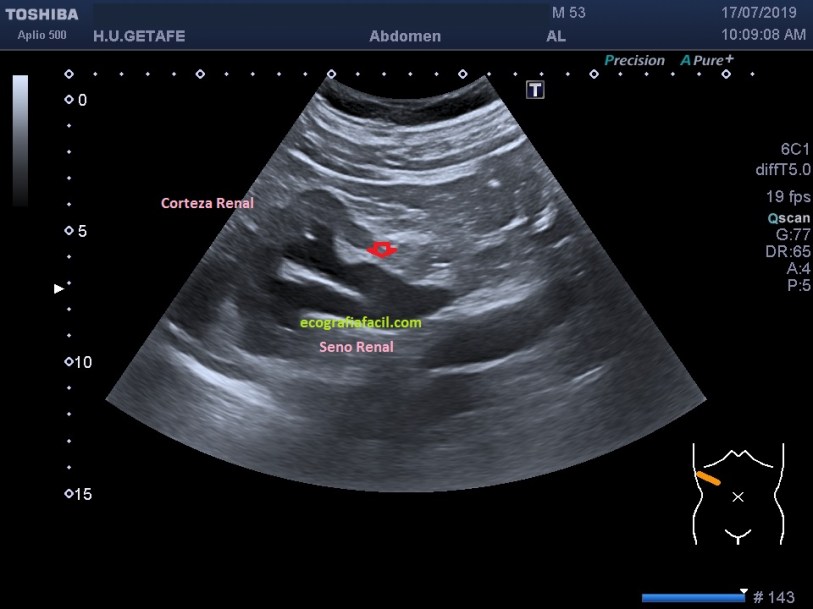

En ocasiones los quistes renales sinusales no tienen una forma de círculo, adoptan este tipo de presencia ecográfica psudoalargada que puedes ver en la imagen 2. Cuando estos quistes son de gran tamaño pueden simular una dilatación. En la imagen 2, podríamos llegar a pensar que el riñón podría estar haciendo una hidronefrosis de bajo grado, pero no, en realidad lo que ves es una gran cantidad de quistes en el seno renal. Demostrar esa especie de «arbolito de brocoli» como en la imagen 1, va a hacer que el diagnóstico sea muy diferente. Recordemos que en ocasiones una uropatía obstructiva con hidronefrosis puede no provocar dolor, igual que los quistes.

3